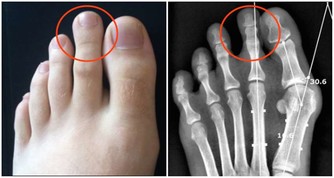

肺怕大便不通。中醫認為,肺和大腸經絡相通,關係密切。具體來說,大便通暢有利於肺氣下行。

比如小兒患肺炎時,如果大便不通,則熱毒不能下瀉排出,肺部的感染和咳喘會明顯加重。

所以治療時都會兼顧通導大便,以使病情減輕,病程縮短。平時宜多進食些芝麻、杏仁等食品,不僅能潤腸通便,還具有養肺利肺之功。